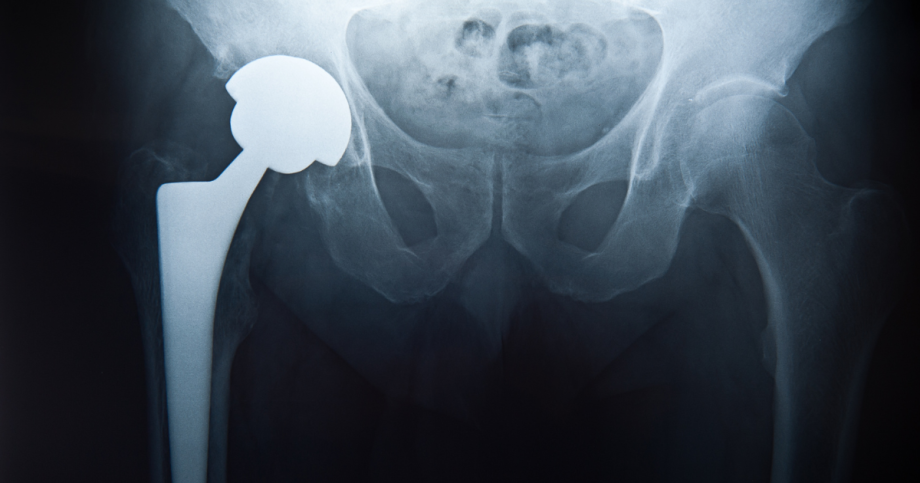

Modern hip replacement isn’t just about replacing a worn joint; it’s about restoring proper function and reducing complications. Precision in component placement is critical for stability, range of motion, and recreating natural hip anatomy.

Choosing the Right Implant: Dual Mobility Hips

Some patients may benefit from dual mobility hip implants, which use a “ball within a ball” design to provide greater stability and range of motion.

How it works:

- A small ceramic ball attaches to the femoral stem.

- A larger polyethylene ball fits over the ceramic ball.

- The polyethylene ball sits within a metal hip socket.